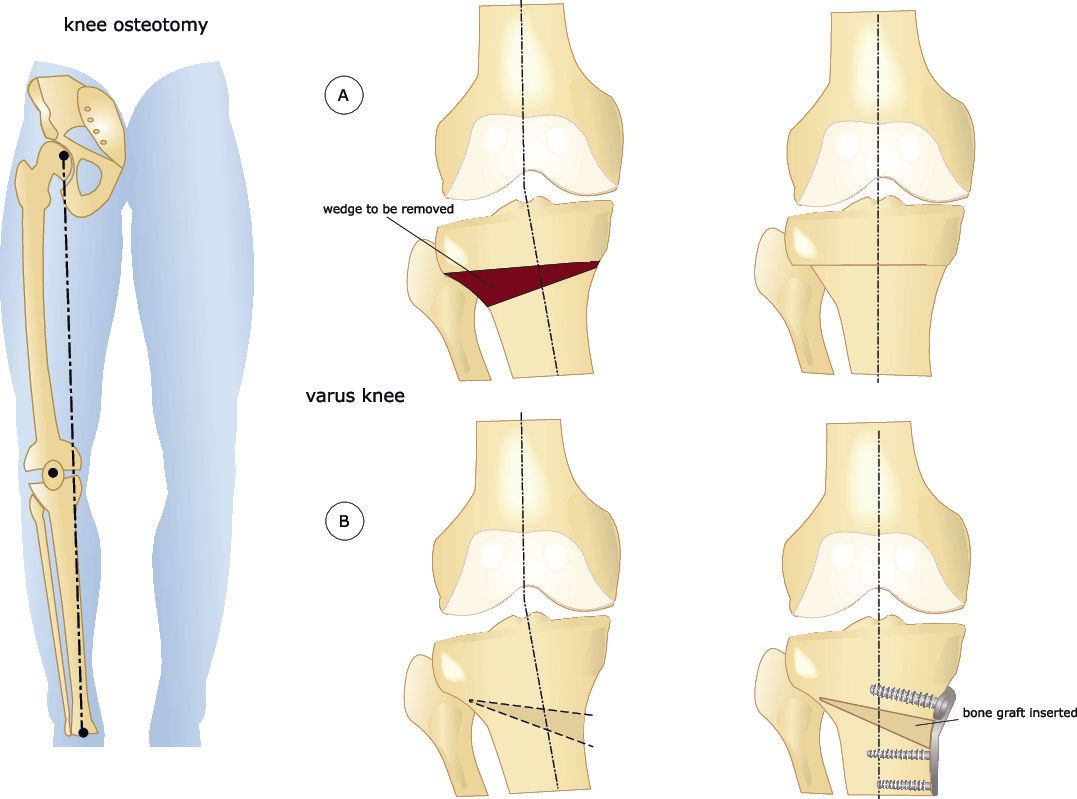

- Η οστεοτομία επανευθυγράμμισης είναι μια διαδικασία που περιλαμβάνει το σκόπιμο σπάσιμο του οστού, την ευθυγράμμιση και σταθεροποίηση στη θέση του με μεταλλικά υλικά (συνήθως μεταλλική πλάκα και βίδες)

- Πραγματοποιείται επειδή υπάρχει διαταραχή της γωνίας του μηριαίου και της κνήμης γύρω από το γόνατο και / ή η φθορά του χόνδρου στη μία πλευρά του γόνατος είναι αρκετά σοβαρή ώστε να συγκεντρώσει τις δυνάμεις βαρύτητας στο φθαρμένο τμήμα του γόνατος

- Με την ευθυγράμμιση του κάτω άκρου οι δυνάμεις βαρύτητας μετατοπίζονται μακριά από το αρθριτικό και επώδυνο μέρος του γόνατος, παρέχοντας έτσι ανακούφιση από τον πόνο

- Υψηλή οστεοτομία κνήμης (high tibial osteotomy):

- Πρόκειται για την τομή της κνήμης κοντά στο γόνατο αλλά χωρίς να επηρεάζεται η αρθρική επιφάνεια του γόνατος

- Επανευθυγράμμιση της κνήμης και συγκράτηση της με μεταλλικά υλικά

- Εφαρμόζεται συνήθως για ραιβογονία

- Τόσο η υψηλή οστεοτομία κνήμης όσο και η κάτω οστεοτομία του μηριαίου μπορούν να πραγματοποιηθούν με:

- Ανοικτή σφήνα:

- Αυτό περιλαμβάνει την πραγματοποίηση ενός απλού κοψίματος στο οστό και το άνοιγμα του κενού

- Κλειστή σφήνα:

- Αυτό συνεπάγεται την πραγματοποίηση δύο κοψιμάτων στο οστό που συγκλίνουν μαζί για να αφαιρεθεί μια σφήνα οστού

- Το κενό κλείνει στη συνέχεια κάμπτοντας το οστό

- Μια ραιβογονία μπορεί να διορθωθεί με μια έσω οστεοτομία ανοικτής σφήνας (πιο συνηθισμένη) ή μία έξω οστεοτομία κλειστής σφήνας της άνω κνήμης

- Μια βλαισογονία μπορεί να διορθωθεί με μια έσω οστεοτομία κλειστής σφήνας (πιο συχνή) ή με μια έξω οστεοτομία ανοικτής σφήνας της άνω κνήμης

- Σε μια οστεοτομία ανοιχτής σφήνας τοποθετείται ένας διαστολέας μέσα στο κόψιμο του οστού και το κενό ανοίγει στον επιθυμητό βαθμό

- Ανάλογα με το μέγεθος του διακένου μπορεί να χρησιμοποιηθεί οστικό μόσχευμα για να γεμίσει το κενό

- Σε μια οστεοτομία κλειστής σφήνας γίνονται δύο τομές στο οστό (αντί για μία) έτσι ώστε να μπορεί να αφαιρεθεί μια οστική σφήνα και στη συνέχεια το οστό να ευθυγραμμιστεί ξανά για να κλείσει το κενό και να ξαναέρθουν σε επαφή τα άκρα του οστού

- Στις οστεοτομίες ανοικτής και κλειστής σφήνας, η οστεοτομία ασφαλίζεται με μεταλλικά εμφυτεύματα που είναι συνήθως πλάκα και βίδες